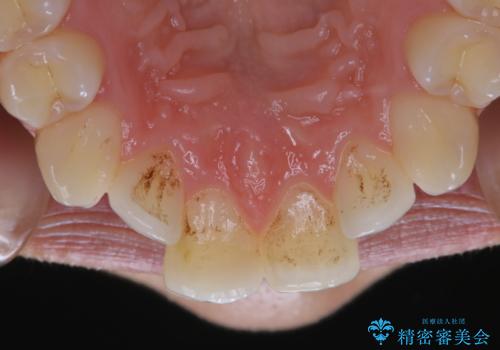

- iTeroスキャン(インビザラインの型どり)をより綺麗にスキャンしたいとのことでした。PMTC(自費クリーニング)30分コースを行い、歯の汚れやステインを取り除きました。

インビザラインの型どりの前に、プラークやステインを除去することで綺麗なスキャニングが行えます。より精度のよいマウスピースを作成するために、PMTCを行うことをおすすめしています。